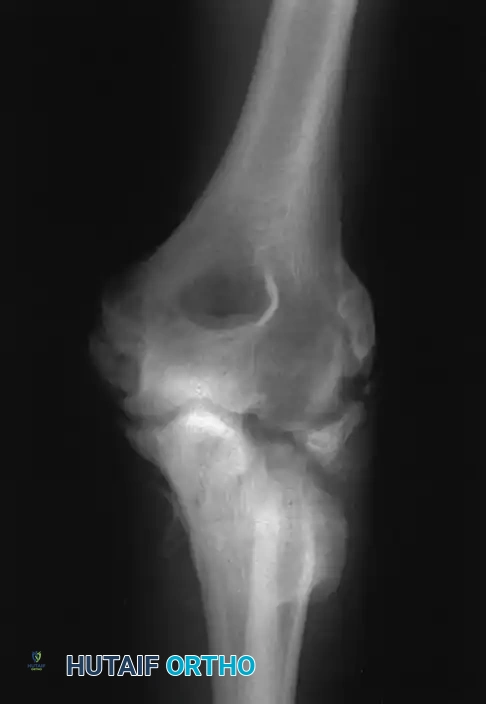

FIGURE 57-69 Extensive heterotopic ossification after a terrible triad fracture-dislocation and radial head excision, resulting in profound stiffness.

Clinical Pearl: HO is typically visible on radiographs 3 to 4 weeks post-injury. Its severity correlates directly with the magnitude of the initial trauma, the degree of soft tissue stripping, and the duration of postoperative immobilization. Prophylaxis (e.g., Indomethacin or localized radiation) should be considered in high-risk patients.